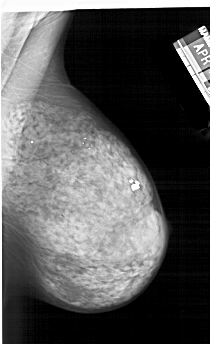

A_1242_1.RIGHT_MLO

RIGHT_CC LINES 5776 PIXELS_PER_LINE 3391 BITS_PER_PIXEL 12 RESOLUTION 43.5 NON_OVERLAY

RIGHT_MLO LINES 6181 PIXELS_PER_LINE 3766 BITS_PER_PIXEL 12 RESOLUTION 43.5 NON_OVERLAY